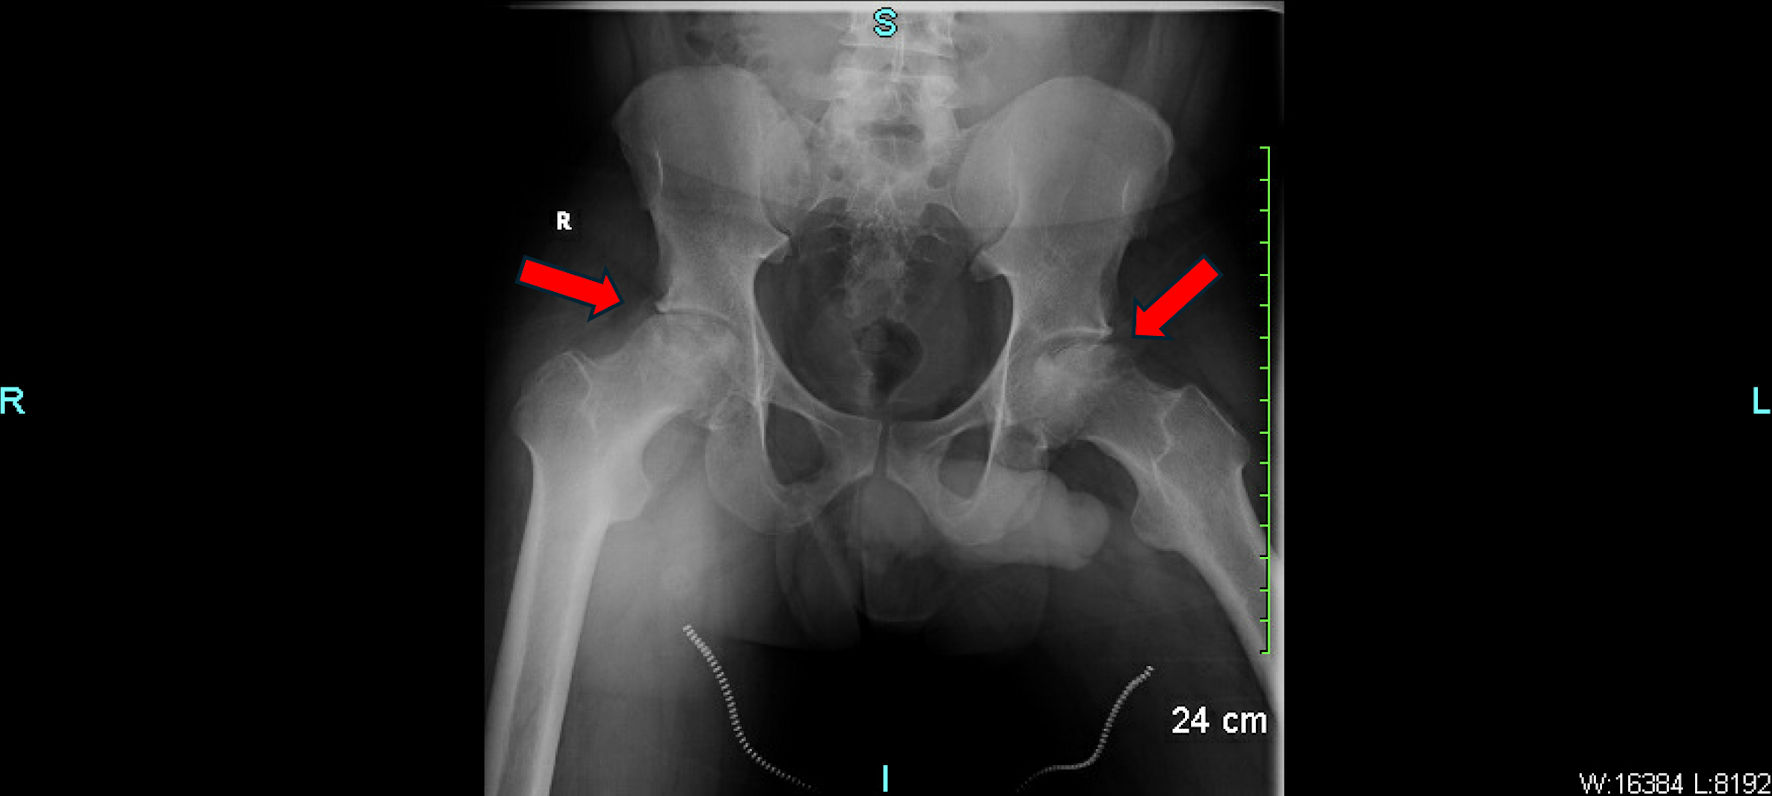

Laboratory results were unremarkable except for an elevated C-reactive protein (8.90 mg/L, reference < 3.01 mg/L). Complete blood count, renal function, liver enzymes, and urinalysis were within normal limits. Hemoglobin was 13.2 g/dL. High-performance liquid chromatography (HPLC) confirmed the diagnosis of SCT (AS pattern), with HbA comprising approximately 60% and HbS approximately 40%, while HbA2 and HbF were within normal limits, consistent with the heterozygous state. Pelvic X-rays demonstrated advanced AVN of both femoral heads, greater than stage II. The left femoral head showed partial collapse, irregularity, and joint space narrowing. No signs of fracture, osteophyte formation, or joint effusion were noted (Fig. 1).

Figure 1. Pelvic X-ray showing advanced avascular necrosis of the bilateral femoral heads with partial cortical collapse. The red arrows indicate areas of sclerotic changes, subchondral lucency, and femoral head flattening consistent with AVN. AVN: avascular necrosis.